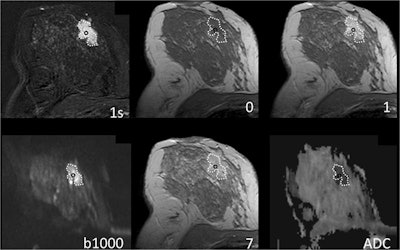

Breast MRI of a 41-year-old woman with grade 2 invasive ductal cancer. Numbers denote acquisition time points of T1-weighted dynamic gradient-echo images after intravenous contrast medium injection in minutes (0 = precontrast acquisition). "1s" equals first subtraction. The dotted line delineates the lesion from the surrounding breast parenchyma. The lesion is depicted as an ill-defined mass with fast initial-phase enhancement and washout during the delayed phase. The region of interest to extract the diagnostic information used in this work is highlighted by a black circle. Images courtesy of Profs. Matthias Dietzel and Pascal Baltzer and European Radiology.Dynamic contrast-enhanced imaging of the initial phase (IP) and delayed phase (DP) is a key part of any clinical breast MRI protocol. However, because DWI has been used increasingly as an add-on sequence, Dietzel's group sought to investigate whether it could be used instead of the delayed-phase part of the protocol.

But adding DWI plus the standard MRI protocol increases scanning time and exam complexity, the researchers explained. They theorized that because the delayed-phase curve type and the apparent diffusion coefficient (ADC) maps obtained from DWI are affected by extracellular space characteristics, perhaps the physiological and diagnostic information they glean would overlap -- thus allowing DWI to be used instead of the delayed-phase part of the MRI protocol.